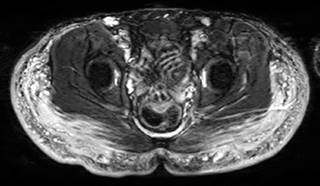

Paciente de 30 años con antecedentes de aplicación de modelantes en las regiones glúteas hace 10 años. Desde hace tres años presenta dolor en ambas piernas, con zonas induradas y cambios de coloración. Se le realizó resonancia magnética de las regiones glúteas y piernas identificando imágenes globulares y lineales irregulares de comportamiento isointenso en el T1, hiperintenso en el T2, hiperintenso en las secuencias de saturación grasa (Fat-Sat) y en STIR (Short Inversion Time Inversion Recovery) con compromiso de los tejidos blandos superficiales y de los planos musculares que afectan a los glúteos mayor y medio (Figuras 1 y 2).

Figura 2: Resonancia magnética regiones glúteas. Coronal STIR. Distribución de los biomodelantes en las regiones glúteas con infiltración de planos musculares